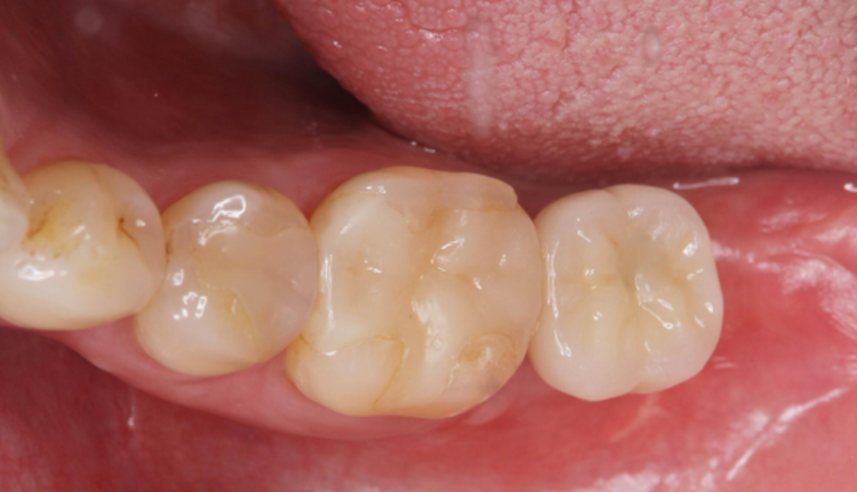

5.Following a 6-month osseointegration period, the implant exhibited favorable bone integration, and the final crown was successfully delivered.

The patient completed the full restoration of Tooth #47 over a 9-month period.